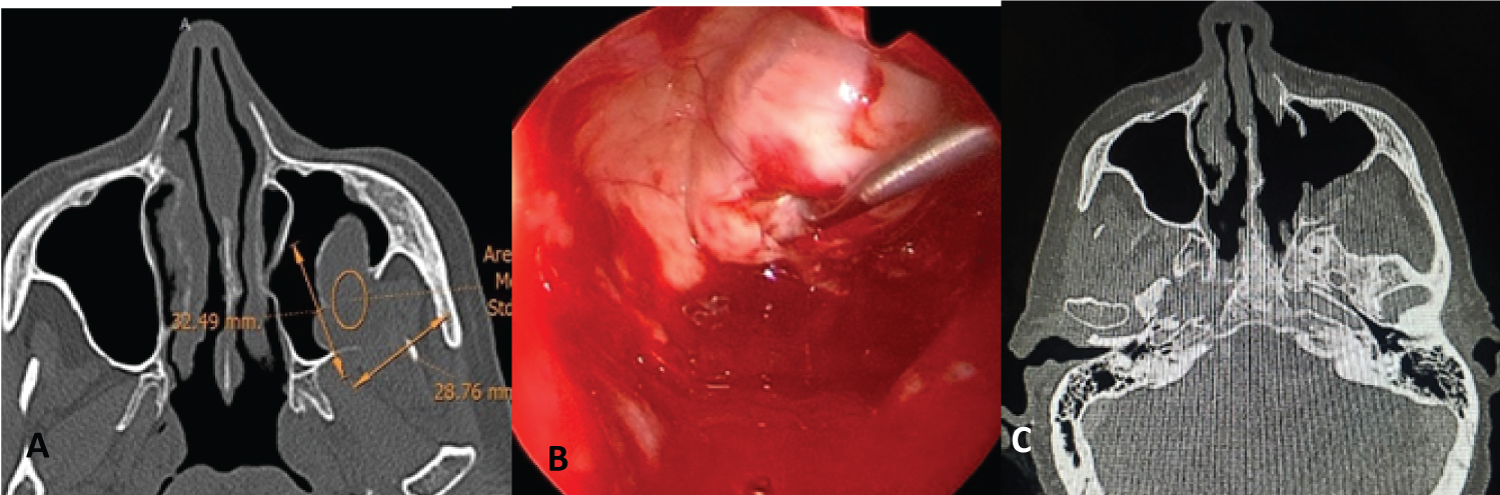

The surgical techniques used varied according to time, before the year 2000 the surgeries were performed using an external approach (Figure 1) or a combination of an external and endonasal approach (cranionasal with endoscopes in conjunction with the neurosurgeon) (Figure 2).

Figure 4: Pterigomaxillary Scwhannoma. A) Axial CT; B) Endoscopic endonasal vision trough middle maxillary antrostomy, scalpel section and intracapsular dissection; C) Postoperative CT. View Figure 4

After year 2000, the endonasal approach was used with 0° and 30° endoscopes. Tumors that were located in the nasal cavity and in the ethmoid were resected through this approach (Figure 3) and in another patient who had a schwannoma located in the maxillary sinus and pterygomaxillary fossa, a wide middle maxillary antrostomy with resection of the posterior wall of the maxillary sinus and an approach to the pterygomaxillary fossa was performed to resect the tumor (Figure 4).

In tumors involving the pterygomaxillary fossa, the endonasal approach with endoscopes is also possible. Using a wide middle maxillary antrostomy, the pterygomaxillary fossa can be approached and complete resections performed, as in the case described in our study.